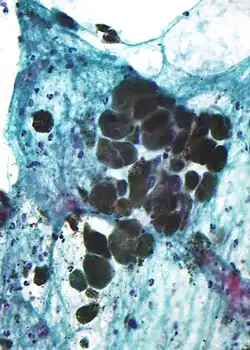

Melanina é uma família de biomoléculas organizadas como oligômeros ou polímeros, que entre outras funções fornecem os pigmentos de muitos organismos.[1] Os pigmentos de melanina são produzidos em um grupo especializado de células conhecidas como melanócitos.

A melanina na pele é produzida pelos melanócitos, que são encontrados na camada basal da epiderme. Embora, em geral, os seres humanos possuam uma concentração semelhante de melanócitos em sua pele, os melanócitos em alguns indivíduos e grupos étnicos produzem quantidades variáveis de melanina. A proporção de eumelanina (74%) e feomelanina (26%) na epiderme é constante, independentemente do grau de pigmentação.[13] Alguns humanos têm muito pouca ou nenhuma síntese de melanina em seus corpos, uma condição conhecida como albinismo.[14]

Como a melanina é um agregado de moléculas componentes menores, há muitos tipos diferentes de melanina com diferentes proporções e padrões de ligação dessas moléculas componentes. Tanto a feomelanina quanto a eumelanina são encontradas na pele e no cabelo humanos, mas a eumelanina é a melanina mais abundante em humanos, bem como a forma mais provável de ser deficiente no albinismo.[15]